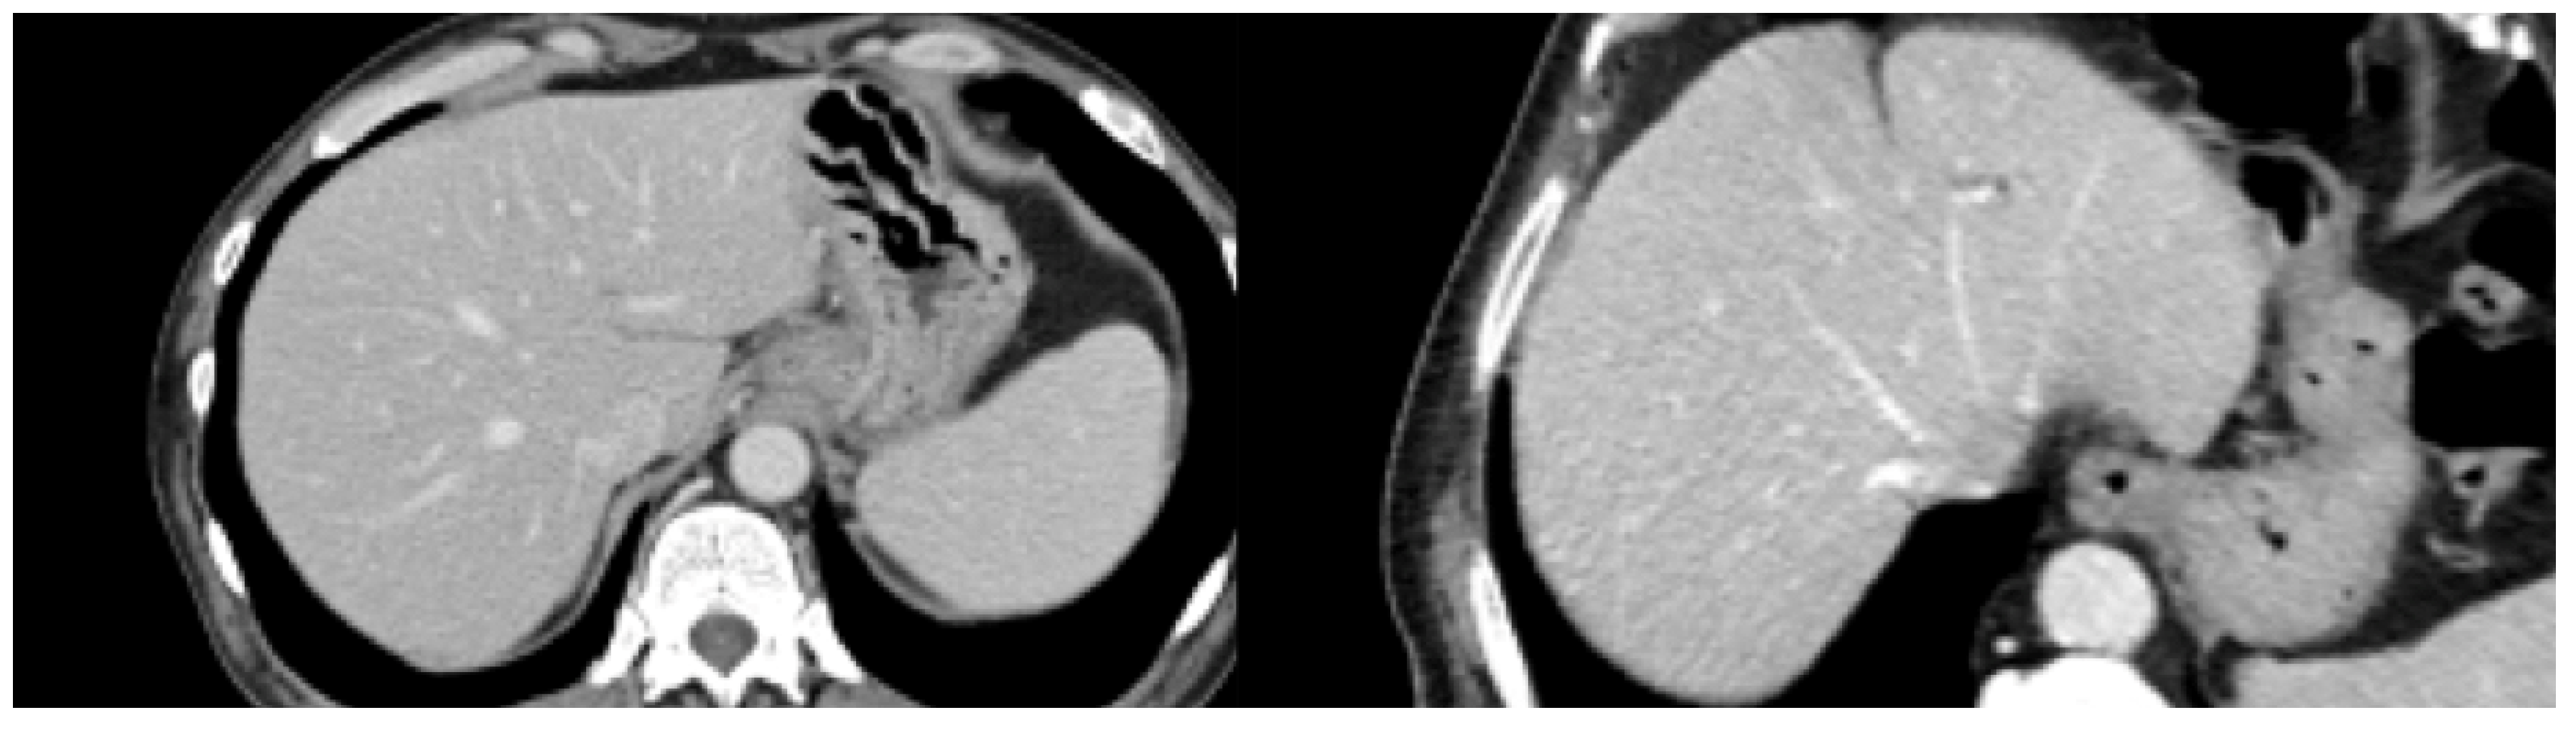

2.2. Image Acquisition and Segmentation